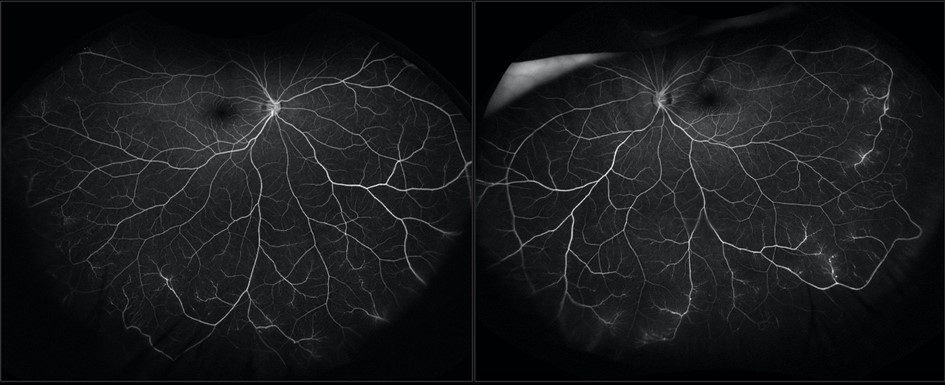

Fluorescein Angiography